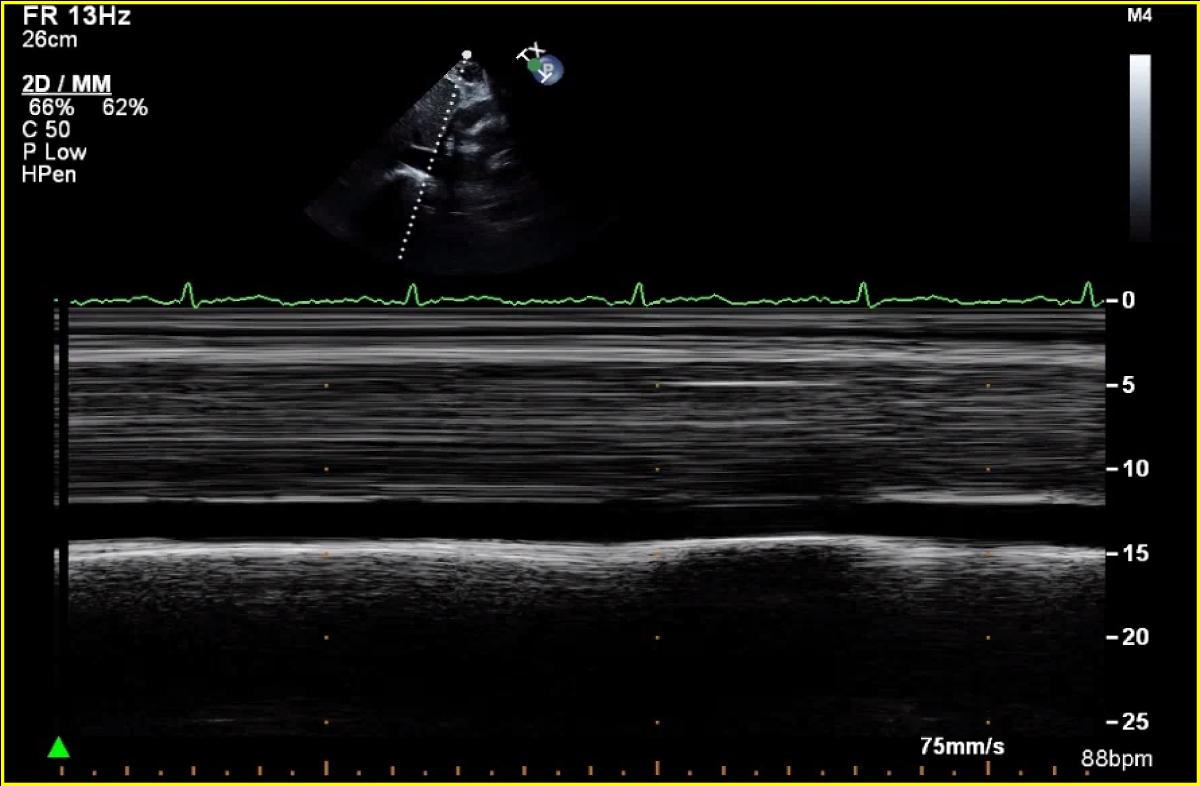

Abstract Body (Do not enter title and authors here): Case Presentation: A 76-year-old male, non-smoker, with history of HLD and NIDDM, presented with several weeks of dyspnea and cough, unresponsive to outpatient treatments. He was normotensive and found to have new onset atrial fibrillation at a rate of 110bpm and pulsus paradoxus with a difference of 15mmHg. CT chest showed a 2.2cm thyroid nodule along with a pericardial effusion (PE), confirmed to be tamponade on TTE (Fig.1). A TTE showed resolution of tamponade after the pericardial window (Fig.2). Pericardial fluid cytology was positive for malignant cells. Patient was discharged, had an outpatient PET CT which showed uptake in the thyroid, pericardial region & right supraclavicular lymph node (LN). The patient developed symptoms of heart failure, prompting his 2nd visit to the hospital after 3 weeks. A repeat TTE showed a small PE with effusive-constrictive physiology (Fig.3). He was started on high dose steroids and diuresed as tolerated, but his symptoms did not improve. He underwent thyroid nodule and right supraclavicular LN biopsy, which revealed high grade follicular thyroid carcinoma (FTC). His course was complicated by multiorgan failure, prompting transfer to another facility for pericardiectomy; during which he was found to have extensive tumor infiltration into the myocardium; he then went into shock and passed away shortly after.